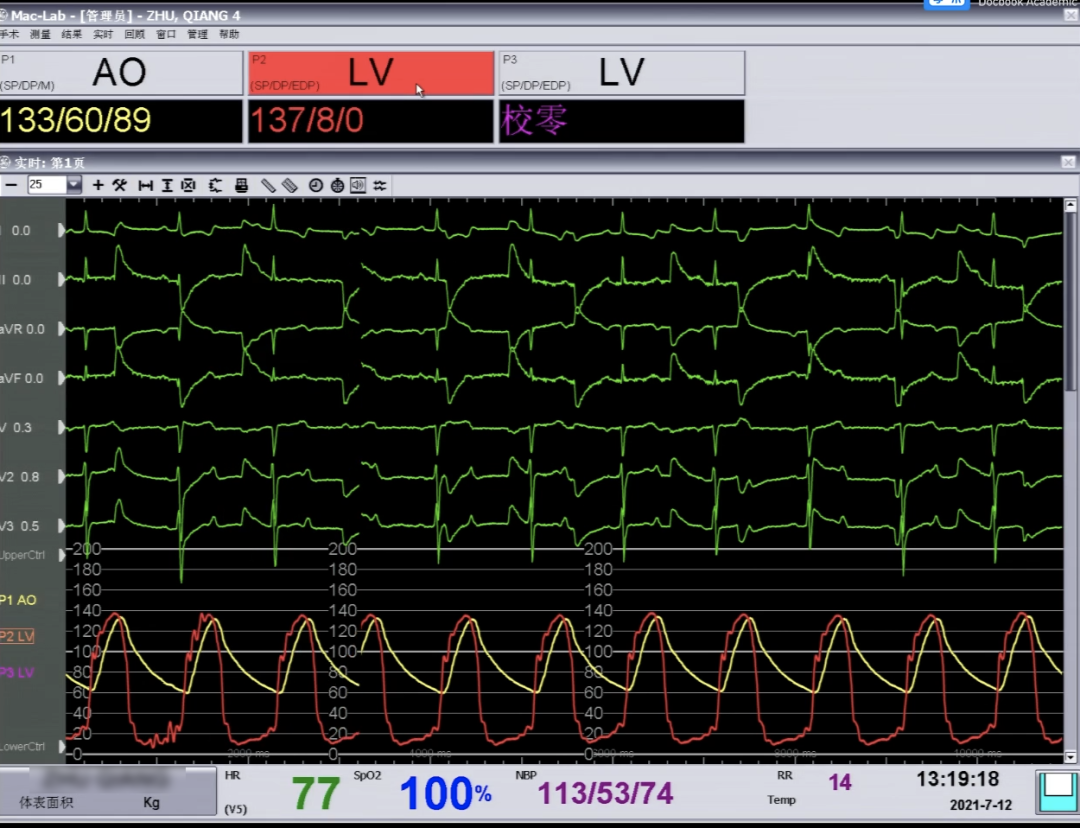

术后即刻评估:

术后平均跨瓣压差降至4mmHg,效果非常好。